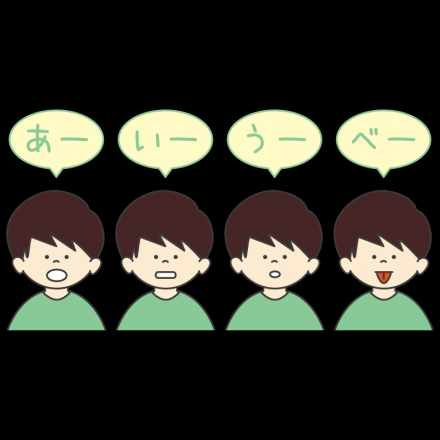

「あいうべ体操」は、小顔にも効果のある誤嚥防止の嚥下体操

-